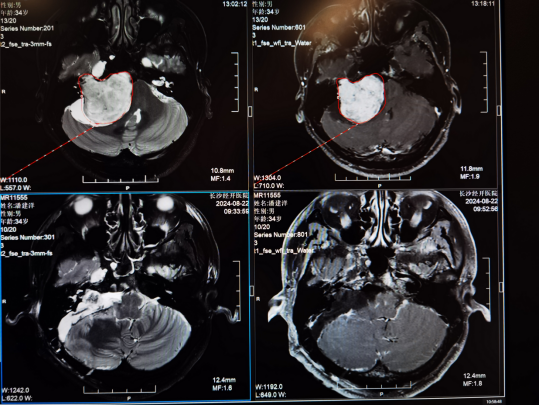

Chi tiết công nghệ chống ung thư